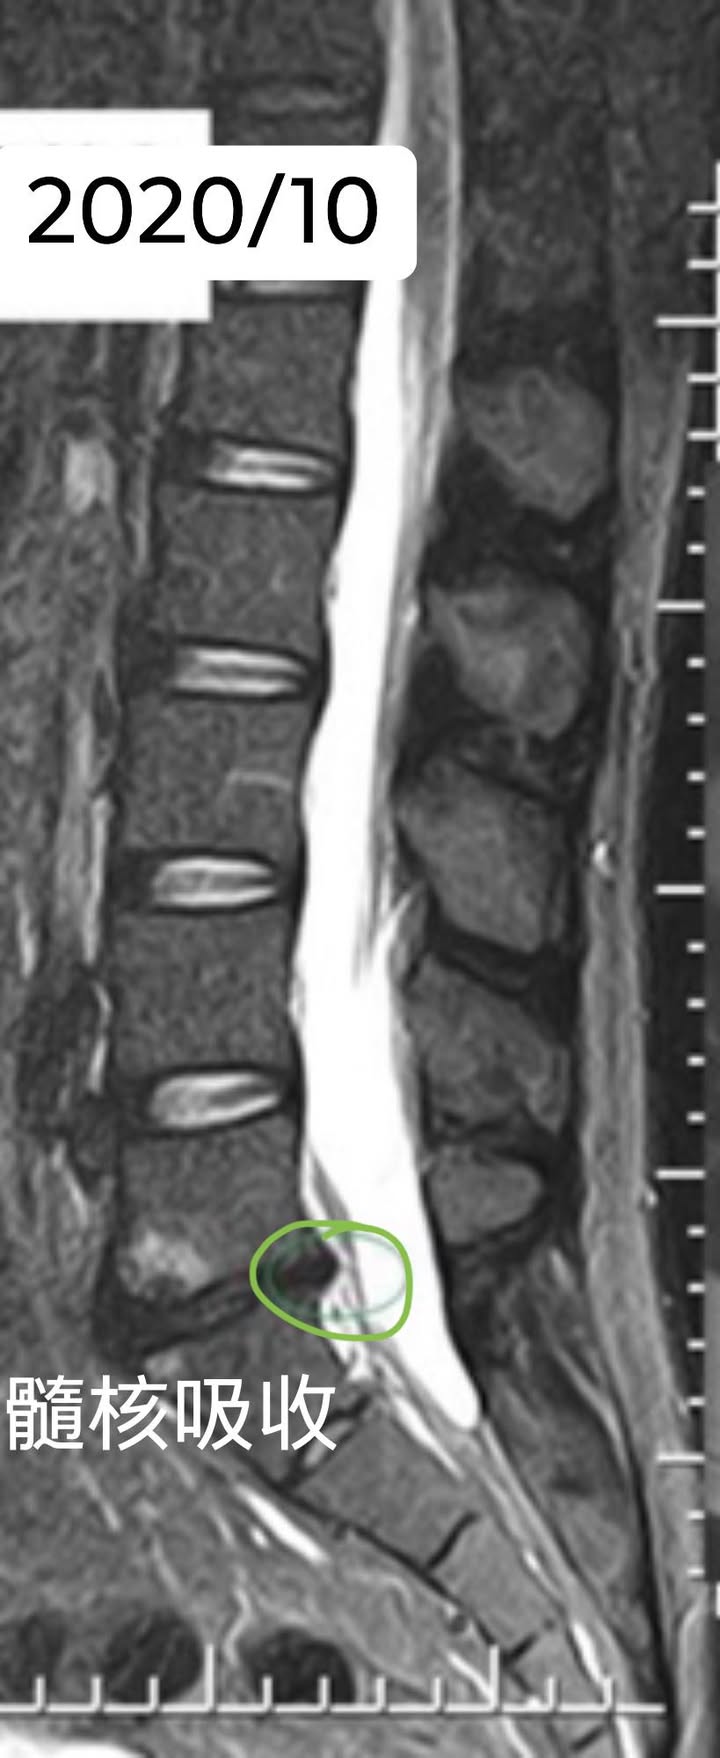

醫案:個案蘇先生從2018/6開始大痛 ,在9月安排MRI,看過好幾個神外醫師都說要開刀,當初痛到無法下床,在2018/9來門診治療,治療三個月後症狀消失,又開始訓練肌力去游泳,到了2019/6月可以開始爬山涉水!一直到2020/8因為其他問題回門診就醫,順便安排MRI看之前腰椎骨刺是否吸收,結果非常驚人

💯感想:脊椎整合中醫微創療法可能是在關節面跟惻隱窩減壓,讓椎間盤內的高壓下降,搭配針灸刺激多裂肌與核心肌群的增生,讓脊上韌帶恢復力量,對抗椎間盤突出,自然提供一個很好髓核自行吸收的環境。